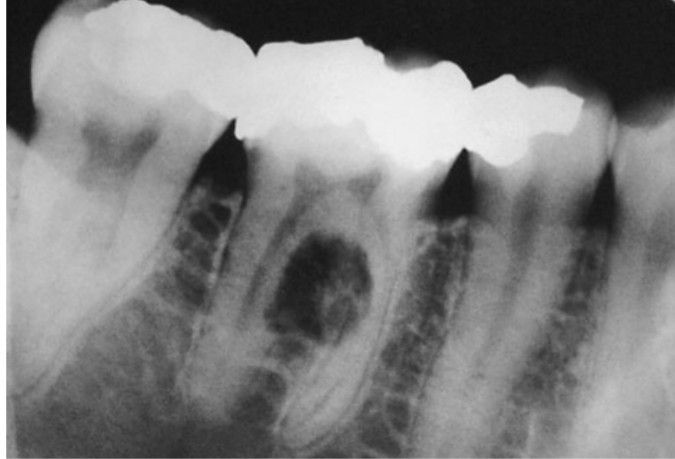

Periapical radiograph demonstrating bone destruction in the furcation of the first molar tooth and associated resorption of the root. A subsequent biopsy specimen demonstrated squamous cell carcinoma, which was diagnosed as a primary intra-alveolar lesion.